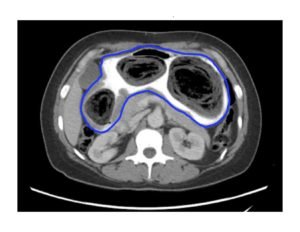

Computed tomography (CT) of the abdomen and pelvis with oral and intravenous contrast was ordered to evaluate her symptoms. The CT showed three large collections of ingested material seen as hypodense material with circular rings surrounded by the hyperdense oral contrast (see red outlines). These findings are consistent with bezoars, the largest of which measured 11.5 x 7.8 cm. There was also thickening of the gastric wall (see blue outline), most notably at the pylorus, consistent with partial obstruction.